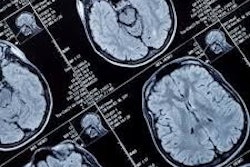

Subtle's imaging solutions complement CorTechs Labs' image analysis products, which integrate with any PET or MRI scanner and PACS. CorTechs' featured brain imaging software, NeuroQuant, uses machine learning to analyze brain structures for automated lesion quantification.